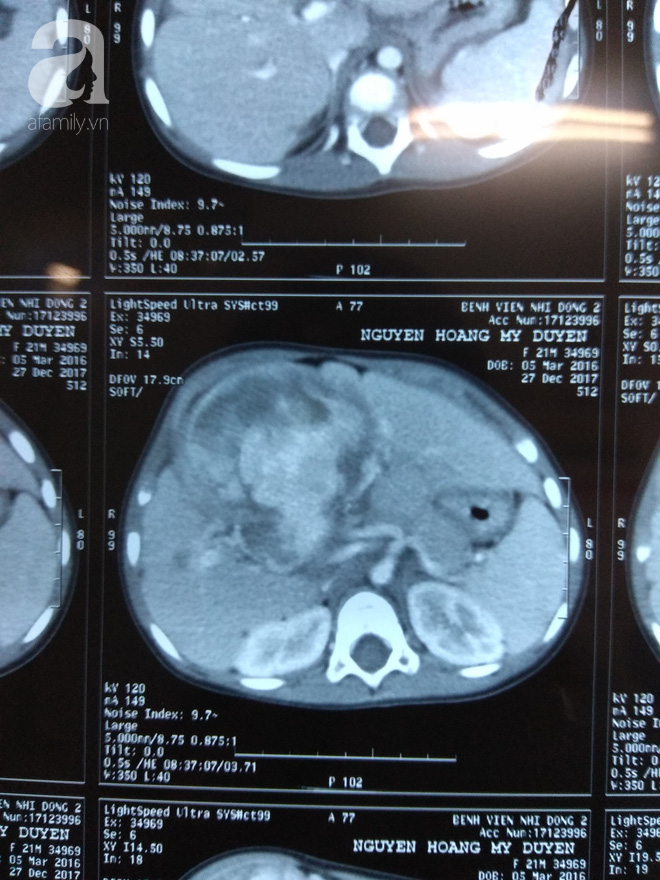

29/06/2018 15:25Bé gái 2 tuổi người Việt mang khối u ác tính ở gan cực hiếm gặp trên thế giới

Đó là trường hợp của bé N.H.M.D (2 tuổi) nhập viện tại Bệnh viện (BV) Nhi Đồng 2 (TP.HCM) trong tình trạng bụng lớn nhanh. Trên phim chụp CT scan vùng bụng cho thấy 1 khối u rất lớn tăng tưới máu rất nhiều chiếm gần hết thể tích của gan. Ngay lập tức, bé được sinh thiết khối u, kết quả cho thấy đây là một khối u ác tính Sarcoma mạch máu.

ThS. BS Vũ Trường Nhân, Trưởng nhóm phẫu thuật ung bướu, BVNĐ2 cho biết Sarcoma mạch máu là một khối u vô cùng hiếm gặp ở gan, chỉ chiếm 1-2% trong các loại u gan ác tính ở trẻ em. Y văn thế giới hiện chỉ ghi nhận khoảng 50 trường hợp được báo cáo.

BS Nguyễn Trần Việt Tánh, khoa Ngoại tổng hợp BV Nhi Đồng 2 phân tích, mặc dù trên hình ảnh, khối u vẫn còn dấu hiệu chèn ép nhiều vào cả 2 nhánh tĩnh mạch cửa của gan nhưng ekip vẫn quyết định phẫu thuật.